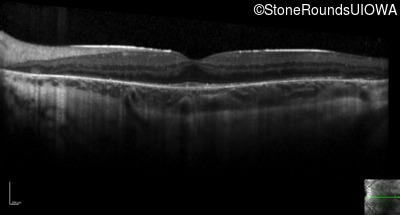

Optical Coherence Tomography - Left - 20/32 -2

Exemplar / OCT Stack